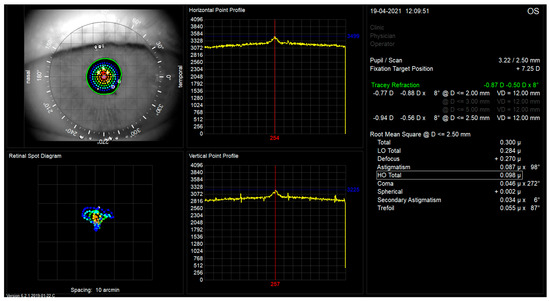

| Tested Parameter | Control Group (Preoperative Measurement) | Patients w/Lentis Mplus15 Lens | Patients w/Lentis Mplus30 Lens | |||

|---|---|---|---|---|---|---|

| Means | SD | Mean | SD | Mean | SD | |

| HOA Total in µm | 0.25 | 0.24 | 0.23 | 0.11 | 0.38 | 0.17 |

| LOA Total in µm | 1.91 | 1.62 | 0.39 | 0.33 | 0.45 | 0.31 |

| Defocus in µm | 0.5 | 2.28 | 0.07 | 0.4 | 0.22 | 0.39 |

| Coma in µm | 0.14 | 0.2 | 0.1 | 0.06 | 0.16 | 0.07 |

| Spherical in µm | 0.02 | 0.09 | 0.05 | 0.03 | 0.02 | 0.06 |

| Trefoil in µm | 0.12 | 0.11 | 0.14 | 0.08 | 0.22 | 0.11 |

| Astigmatism in µm | 0.58 | 0.71 | 0.25 | 0.18 | 0.28 | 0.14 |

| Secondary Astigmatism in µm | 0.04 | 0.04 | 0.04 | 0.03 | 0.06 | 0.04 |